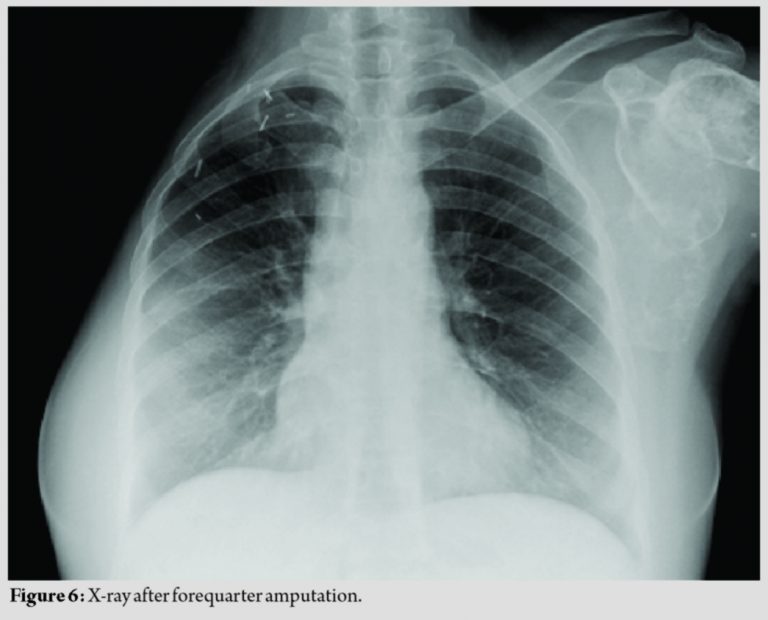

After clinical, radiological, and histopathologic review at our joint clinic meeting, a diagnosis of polyostotic FD was made and the patient was worked up for a forequarter amputation (Fig. 5 and 6).

The patient, after a follow-up of 2 years, is asymptomatic for her other lesions (Fig. 7).